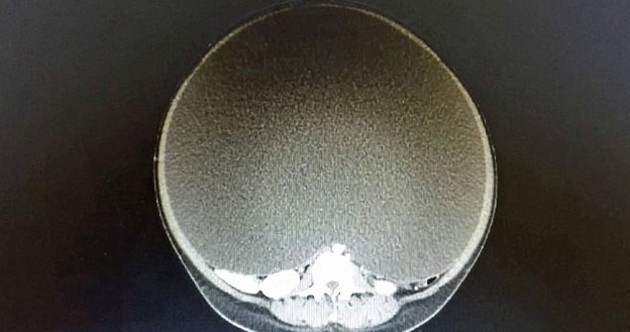

24 yaşındaki Amerika'da yaşayan bir kadın, diyet yapmasına rağmen gittikçe kilo aldığını fark etti. Ancak tuhaf olan yüzü, kolları ve bacakları zayıflarken karnı günbegün şişiyordu.

Karnındaki şişlik organlarını o kadar rahatsız ediyordu ki birkaç adım attıktan sonra acı içinde nefes nefese kalıyordu.

Doktora giden Meksikalı kadının yumurtalık kistinin olduğu ortaya çıktı.

11 aydır büyüyen kitle, operasyonla alınana kadar 33 kiloya ulaşmıştı. Kalp krizi riskiyle karşı karşıya olan kadının iç organları ciddi oranda hasar görmüştü.